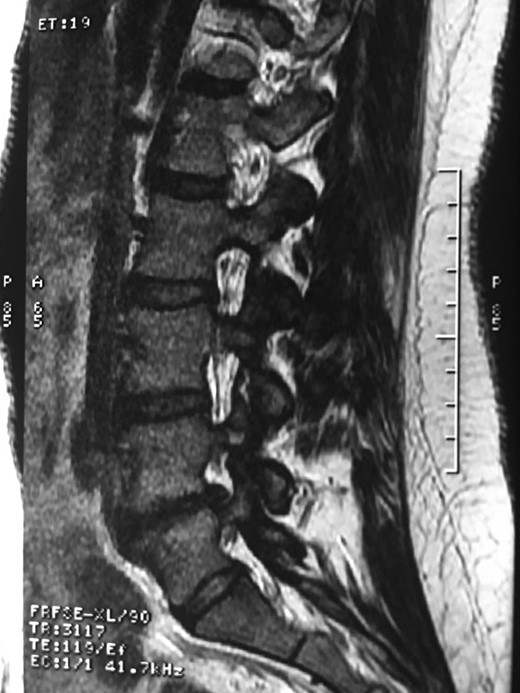

A 42-year-old female presented to the clinic with a history of chronic low back pain. She reported no relevant medical history. She had already been treated in the last 4 years by general practitioners with analgesics and home based physiotherapy with no satisfactory results. She had two previous admissions to the emergency department where morphine was prescribed to control the pain on her lower back. She was under ambulatory treatment with diclofenac, and tizanidine with partial relief of symptoms. Her main complaint was pain on the lower lumbar back with no radiation to the lower extremities. In her physical evaluation she presented limitation to full rotation and bending of the lumbar spine due to pain. Lasegue sign was negative, sensitivity, reflexes, sagittal balance, distal muscular strength and pulses were normal. Radiographs showed an overdeveloped left transverse process of the fifth lumbar vertebra which contacts with the sacrum at the left sacral wing with signs of degeneration at the same site (Fig. 1). Magnetic resonance imaging (MRI) studies were obtained (Figs 2–5). The patient was taken to the operating room where infiltration with 1 mL of lidocaine and 40 mg of Triamcinolone was performed in the pseudoarticulation between the left transverse process and the sacrum under fluoroscopic guidance. She reported a complete relief of pain after the procedure. At three months follow-up she was managed with strengthening and stabilizing exercises for the lumbar spine and postural education was initiated. She remains asymptomatic at her 12 months follow up.

RMN of the patient showing smaller facets in the anomalous articulation and healthy disc compared to the supradjacent one (next figure).

The partial fusion at the lower part of the lumbosacral transition produces important alterations in normal biomechanics at the levels immediately above and below the LSTV. Changes such as hypermobility and abnormal torque moments are present at the level above the LSTV, predisposing it to early degeneration (early disc pathology and facet joint degenerative disease). Restricted movement below the LSTV produces a protective effect against degeneration of disc and facets and is related to changes (facets are smaller and coronally oriented) in the dimensions of the lower level facet joints [7]. These alterations can be verified in the adjacent levels of the LSTV in our patient.